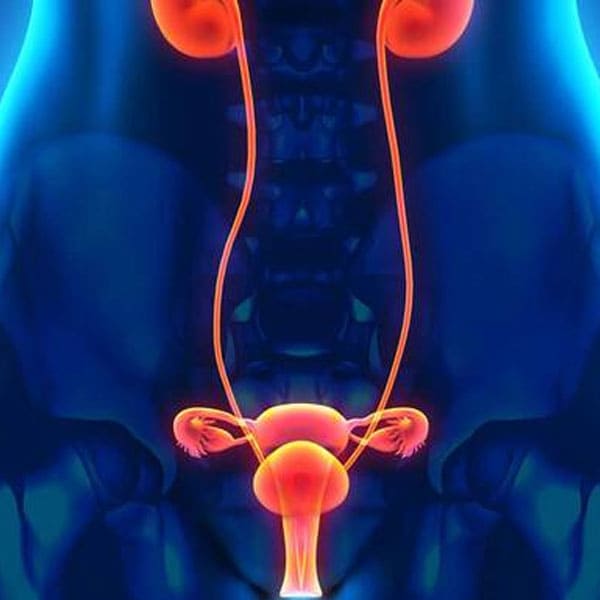

Que son los riñones

Realización de ultrasonido renal

Es un examen seguro y sin dolor el cual permite al nefrólogo ver imágenes de los riñones y la vía urinaria.